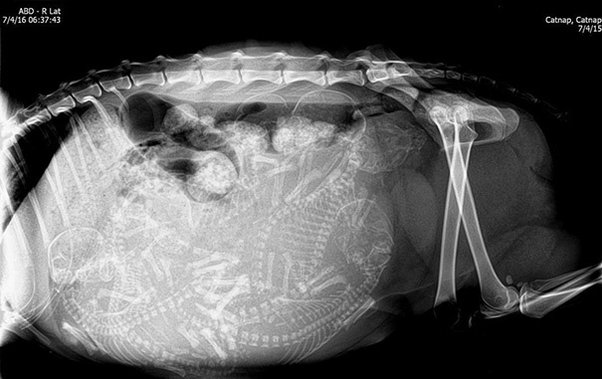

مجموعة من الصور بالأشعة السينية لبعض الحيوانات، معظمها في حالة الحمل.

الصور بالفعل مذهلة، سبحان الله العظيم.

3️⃣ قطة حامل.